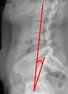

Cobb Angle

Thoracic Kyphosis (T5–T12 Cobb)